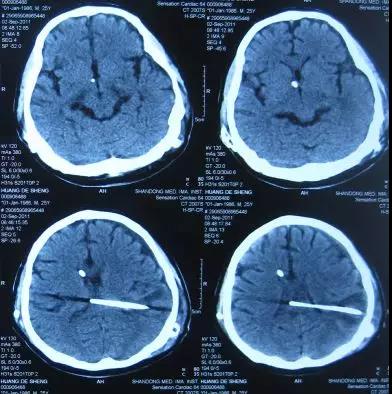

医生给予保守治疗十余天后症状仍无改善,2011年8月30日进行了第2次左侧脑室-腹腔分流术,术后第2天即2011年9月2日,症状改善,可以简单言语和活动,头部CT示脑室缩小(图-4)。

图-4:2011年9月2日头部CT